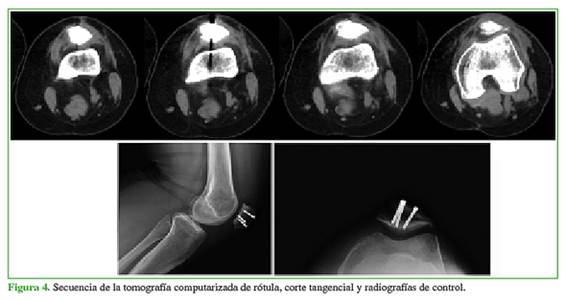

Mujer de 32 años con dolor crónico de origen rotulofemoral en la rodilla izquierda y limitación para caminar en superficies inclinadas. Las radiografías anteroposterior y lateral de rodilla, y tangencial de rótula mostraban cambios artrósicos de la rótula (Figura 1). En enero de 2018, una resonancia magnética de rodilla reveló una lesión condral de la rótula grado IV. Se indicó rehabilitación e infiltración con corticoides, pero el dolor no mejoró (Figura 2). El 13 de febrero de 2018, fue sometida a una cirugía con aloinjerto fresco de rótula (Figura 3). La evolución fue satisfactoria, sin dolor ni derrame articular, los arcos de movilidad eran de 0° a 100°, no tenía limitaciones para caminar. En la radiografía y la tomografía computarizada de rótula (septiembre de 2018), se observó la incorporación del injerto (Figura 4).